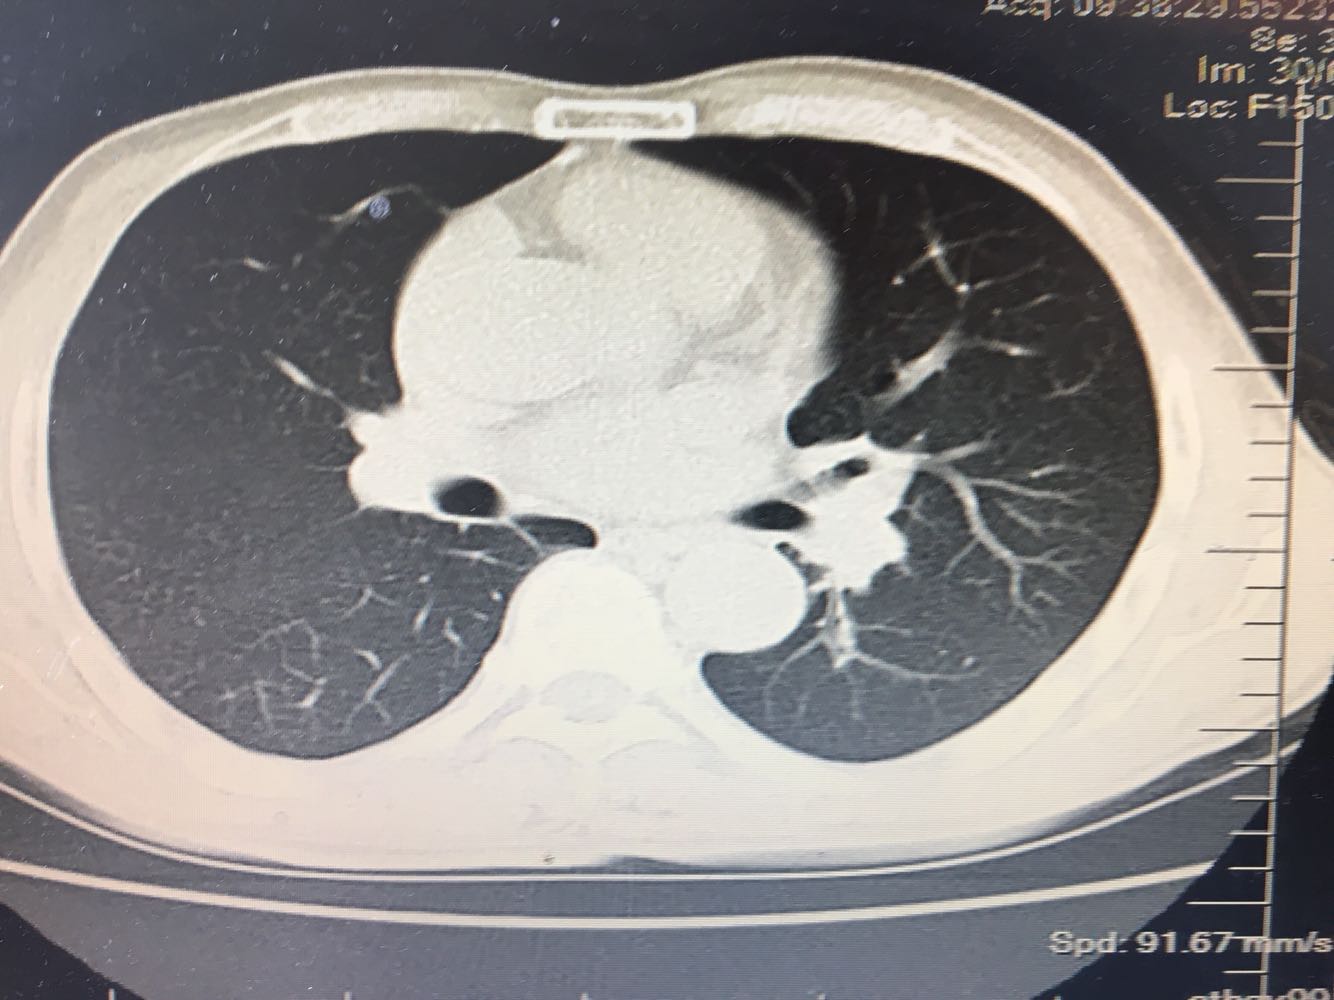

左肺下叶鳞癌

男,63岁,咳嗽1个月入院,患者自述1个月前无诱因咳嗽,阵发性干咳,无痰,时有血丝,无发热,左胸痛,活动后气短,静滴头孢13天无好转,门诊查肺CT后以 肺占位收入我科,病来饮食睡眠可,体重明显下降。既往疝气术后1年,吸烟史30年,每日1包。

左肺癌

左肺中央型肺癌,是否可以手术,还是化疗,放疗,靶向治疗?